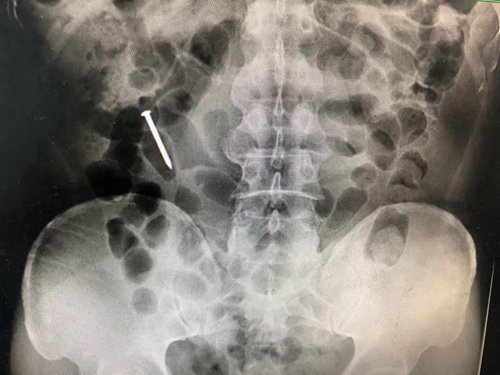

腹部X片检查:发现钉子,但不能确定具体位置;

CT检查:在罗锋空肠中下段部位发现了钉子。

通过前期的肠道准备,5月14日,杨伟兴再次安排罗锋做了腹部CT检查,结果提示钉子已经滑落至回盲部。时机正好,杨伟兴立即准备为罗锋做急诊结肠镜检查。

10分钟后,杨伟兴从罗锋回盲部顺利取出一根35mm的钉子。而此时距离罗锋误吞钉子已过去了43个小时。